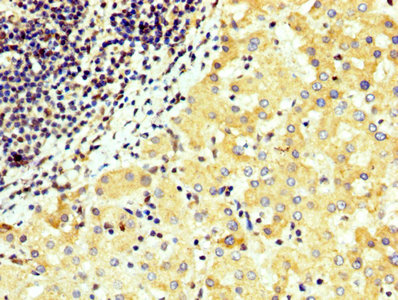

Immunohistochemistry of paraffin-embedded human testis tissue using CSB-PA026137LA01HU at dilution of 1:100

IHC image of CSB-PA026137LA01HU diluted at 1:300 and staining in paraffin-embedded human liver cancer performed on a Leica BondTM system. After dewaxing and hydration, antigen retrieval was mediated by high pressure in a citrate buffer (pH 6.0). Section was blocked with 10% normal goat serum 30min at RT. Then primary antibody (1% BSA) was incubated at 4°C overnight. The primary is detected by a biotinylated secondary antibody and visualized using an HRP conjugated SP system.